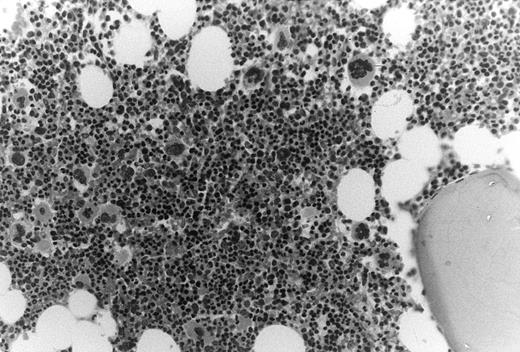

In these thrombocytopenic HIV-infected patients the number of marrow megakaryocytes was increased nearly threefold, ie, 30 ± 15 × 106/kg compared with 11 ± 2.1 × 106/kg (P = .02). Bone marrow biopsy specimens showed normal cellularity with increased ratios of morphologic megakaryocytes to nucleated erythroid cells (Fig 2).

Increased megakaryocytes in bone marrow biopsy samples obtained from HIV-infected patients with thrombocytopenia. In this cohort of thrombocytopenic HIV-infected patients bone marrow biopsy samples typically showed normal to abundant megakaryocytes; megakaryocyte/erythroid ratios were typically increased.

Flow cytometric megakaryocyte quantitation documented a threefold expansion in marrow megakaryocyte substrate available for platelet production in these thrombocytopenic HIV-infected patients (Table 2). Estimates of increased megakaryocytopoiesis were also evident from the marrow biopsies (Fig 2). We attribute this amplification in marrow megakaryocyte mass to stimulation by endogenous TPO (Table 2), because endogenous TPO was significantly elevated in these patients (Table 2). However, the reduction in the number of marrow megakaryocyte progenitors in these patients implies a direct effect of HIV on megakaryocyte development (Table 2). The decreased frequency of megakaryocyte progenitors within the CD34+ population in the marrow of HIV-infected patients is comparable to the reduction in CFU-Megs found in the marrow of chemotherapy patients undergoing autologous bone marrow transplantation. This reduction in marrow progenitors may be due to inhibitory effects of HIV on the proliferation of marrow hematopoietic progenitor cells.